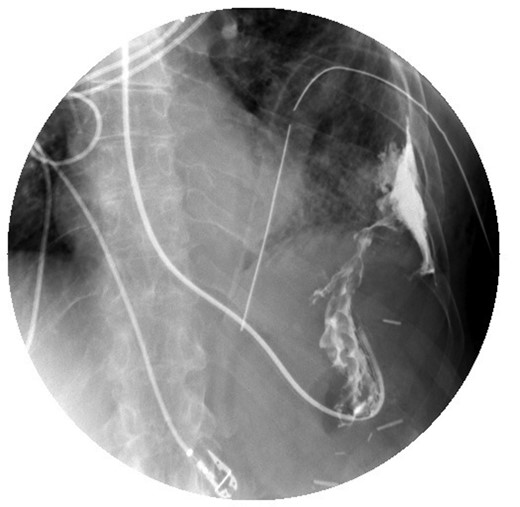

Bilious drainage was noted from her chest tube. An upper GI series with gastrografin demonstrated a gastropleural fistula (Fig. 2). General surgery was consulted for possible surgical management. The patient was started on total parental nutrition, broad-spectrum antibiotics and antifungal therapy. Her respiratory status improved and she was extubated on hospital Day 4.

Upper GI study demonstrating contrast administered via nasogastric tube with extravasation into the pleural space.